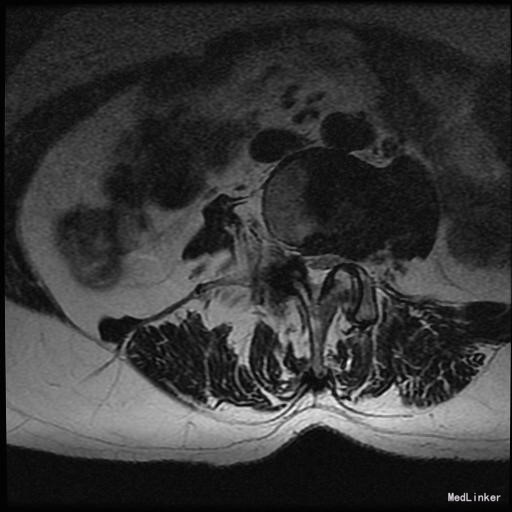

主诉:右下肢麻木11年,腰部酸痛无力 现病史:女性患者,65岁,患者于11年前无明显诱因下出现右下肢麻木,自大腿至右踝部,站立位加重。未予重视,后期出现腰臀部僵硬,弓背僵硬无力,自主行走距离不足200米,曾于06年经X线平片及MRI检查:腰椎椎管狭窄伴有腰椎滑脱,椎间盘突出等。

查体:侧弯畸形,右臀部及右下肢麻木疼痛,腰部活动受限,难以站立。右侧支腿抬高试验60°。双下肢肌力肌张力可。 辅助检查:平片:腰椎侧弯,椎体滑脱,曲度后凸 磁共振:L2-3,L4-5,L5-S1腰椎椎管狭窄,l2-3L3-4L4-5L5-S1腰椎间盘突出,腰椎退变

诊断: 腰椎侧弯,腰椎间盘突出 治疗:1期微创侧路椎体融合术+2期 微创后路经皮内固定术